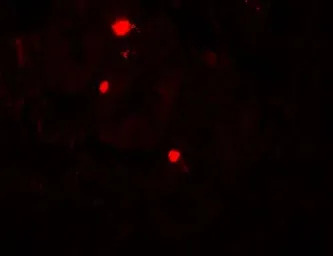

IHC-P analysis of human small intestine tissue using GTX31498 ATG14 antibody.

Working concentration : 20 μg/ml